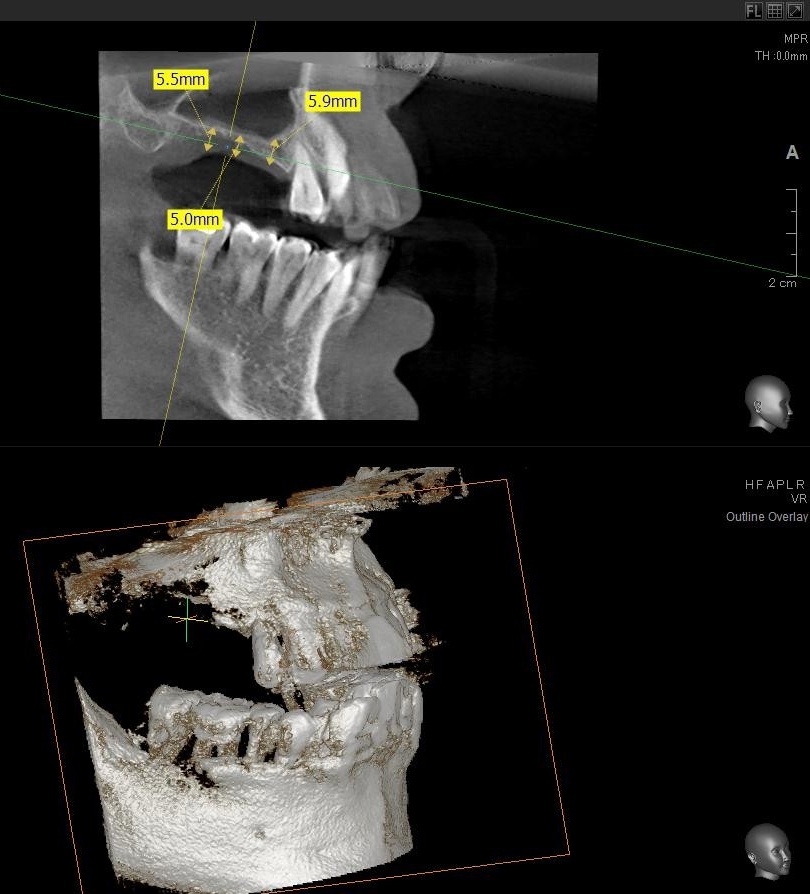

今回の患者様はインプラント植立を希望され、右上5番目・6番目・7番目の3本の植立が決まりました。

ドリルの先端を細い物から徐々に大きい物に変えながら、植立するインプラント体のネジの部分を除いた胴の部分の太さに合わせた大きさの穴を開けていきます。

開けた穴に、専用道具を使ってネジを締めるように長さ2センチ程のインプラントを骨に埋め込んでいきます。